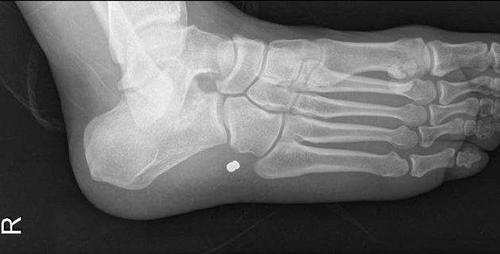

También hay varios ejemplos de heridas traumáticas, desde palos hasta balas pasando por espinas de pescado.